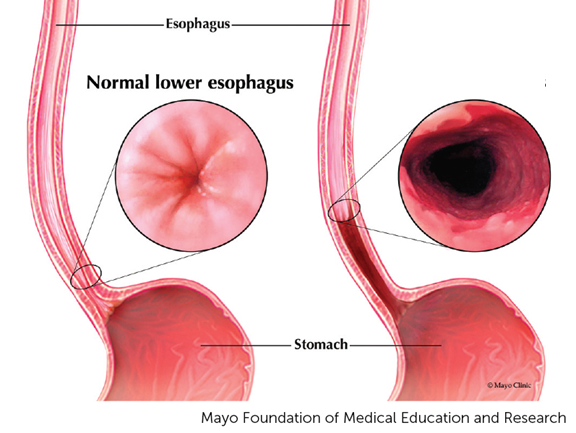

Gastroesophageal Reflux

This disease occurs when the cardiac sphincter does not completely close, stomach acid and contents reflux back into the esophagus.

When the condition is chronic and permanent changes to the esophagus occurs, it is called ________.

This is caused by scarring of the distal esophagus by chronic reflux.